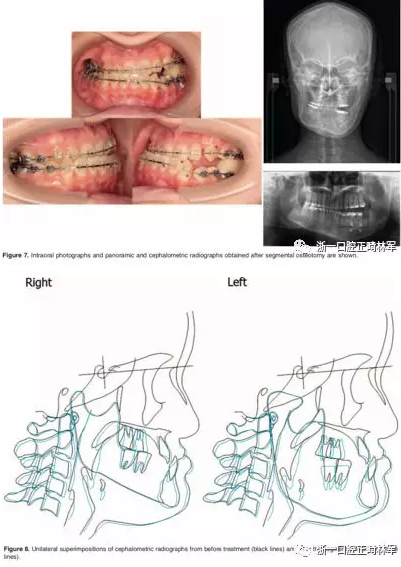

第二阶段:14个月后,进行左侧下颌骨节段性截骨术。在手术中,使用超声骨刀,在左侧后牙区在第一前磨牙处截去3 mm,在第一磨牙区截去6 mm,随后用钛板固定,并立即上0.019*0.025不锈钢丝。下颌合平面和Go-Go'平面从而平行,严重的牙槽骨代偿得以矫正。由于上磨牙和下磨牙之间出现间隙,粘接咬合板以保持颌间间隙,并在这一阶段期间帮助维持左侧咀嚼效能(图7和8)。在这一阶段,患者的面部外观几乎没有变化。